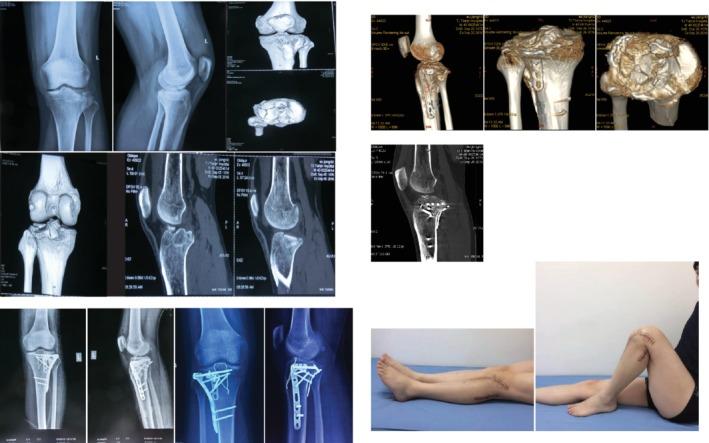

To summarize the indications and the clinical effects of a transfibular neck osteotomy approach and a combined anterolateral and posterolateral approach in the treatment of fractures of the lateral tibial plateau involving the posterolateral column.

Eleven patients with lateral tibial plateau fractures were included in the present study. The fractures were Schatzker type II or lateral platform fractures involving posterolateral column. The anterolateral combined posterolateral approach (lateral + posterolateral locking plate fixation) was applied in 7 patients and 4 patients underwent transfibular neck osteotomy (lateral + posterolateral locking plate fixation + 1/4 tubular plate edge fixation, fibular osteotomy with Kirschner wire tension band fixation, and hollow nail fixation for upper tibiofibular joint). All cases were followed up for 12-24 months, with an average follow-up of 17.5 ± 5.0 months. At the last followup, the Rasmussen radiological criteria were used to evaluate the effect of fracture reduction and fixation. The knee joint function was evaluated using the knee function evaluation criteria of the Hospital for Special Surgery (HSS). The Lachman test and the pivot-shift test were used to evaluate the anterior and posterior and rotational stability of the knee joint. The range of knee motion was recorded.

Bone healing was achieved in all patients with fractures treated with a transfibular neck osteotomy approach and a combined anterolateral and posterolateral approach. At the last follow-up, both the Lachman test and the pivot-shift test results were negative. All patients had complete knee extension. For the combined anterolateral and posterolateral approach, the knee flexion angle was 110°-130°, with an average of 122.86° ± 7.56°. For the transfibular neck osteotomy approach, the knee flexion angle was 115°-130°, with an average of 120.00° ± 7.07°. For the patients in which the combined anterolateral and posterolateral approach was used, the Rasmussen score was 12-18 points, with an average of 16.00 ± 2.56 points. The results were excellent in 4 cases and good in 3 cases; therefore, 100% of results were excellent or good. For patients in which the transfibular neck osteotomy approach was used, the Rasmussen score was 10-18 points, with an average of 15.25 ± 3.77 points. The results were excellent in 2 cases, good in 1 case, and acceptable in 1 case; therefore, 75% of results were excellent or good. The HSS score for the combined anterolateral and posterolateral approach was 76-98 points, with an average of 88.43 ± 7.55 points. The results were excellent in 5 cases and good in 2 cases; therefore, 100% of results were excellent or good. The HSS score for the transfibular neck osteotomy approach was 74-96 points, with an average of 87.25 ± 9.43 points. The results were excellent in 3 cases and good in 1 case; therefore, 100% of results were excellent or good. There were no significant differences in operation time, surgical blood loss, fracture healing time, postoperative imaging score, and knee function evaluation between the two approaches. One patient who underwent transfibular neck osteotomy had a 3-mm step that gradually appeared, but no significant abnormalities were found in the width of the platform and the lower limb force line. One patient in whom the combined anterolateral and posterolateral approach was used showed numbness in the common peroneal nerve. No common peroneal nerve injury occurred through the transfibular neck osteotomy approach.

The anterolateral combined posterolateral approach and the transfibular neck osteotomy approach are effective in the surgical treatment of lateral tibial plateau fractures involving the posterolateral column. However, the transfibular neck osteotomy approach is more suitable for the posterolateral plateau articular surface damaged with bone separation and displacement, deep collapse, cases involving a large range of the posterolateral column, especially fractures of the lateral tibial plateau in the upper tibiofibular syndesmosis area of the line connecting the anterior and posterior margin of the fibular head to the midpoint of the plateau.